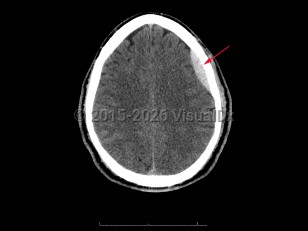

Epidural intracranial hematoma

The classic presentation involves a brief post-traumatic loss of consciousness, then several minutes to hours of a lucid interval, followed by obtundation and focal neurologic deficits. While this classic clinical description is widely taught, it is seen in < 20% of cases. Other less specific signs and symptoms include headache, nausea and emesis, seizures, neurologic deficits (contralateral weakness, hyperreflexia), papilledema, pupil-involving third-nerve palsy, somnolence, or coma.